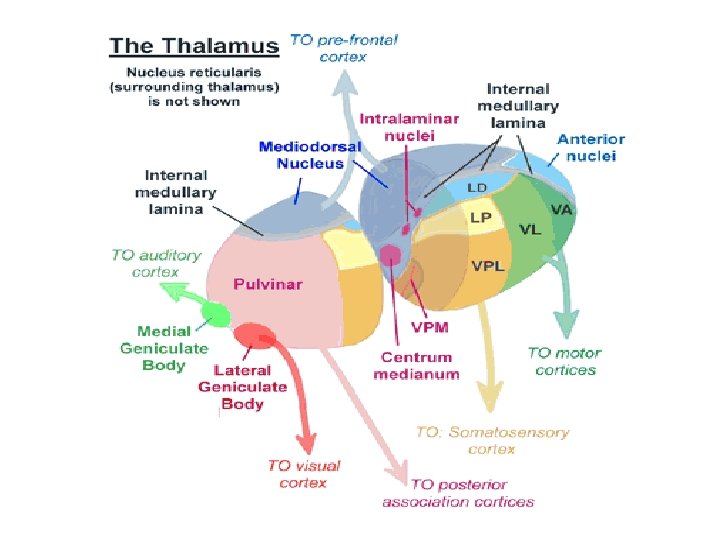

Integrated Circuitry Linking Temporal, Diencephalic, and Basal Forebrain Regions